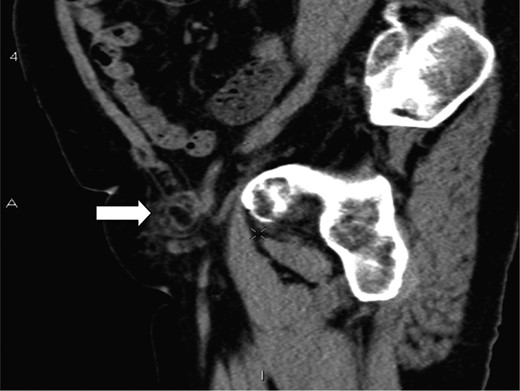

A saggital section demonstrating the tip of the appendix (white arrow) within the femoral sac.

On examination, she was overweight and a non-tender swelling was palpable in her right groin. It was ∼4 cm in size, soft but not reducible and located below the groin crease. Bloods revealed a marginally elevated white cell count and CRP. She consented to an emergency open repair of her femoral hernia and appendicectomy. Her hernia was approached via a groin crease incision; however, it was difficult to dissect to the base of the appendix. A decision was made by the operating surgeon to complete her femoral repair using a mesh plug since the appendix appeared normal with no free fluid or inflammatory changes. Her appendix was removed laparascopically. Post-operatively, she recovered well and was discharged on the second day after her operation. Pathology report showed an acutely inflamed appendix.